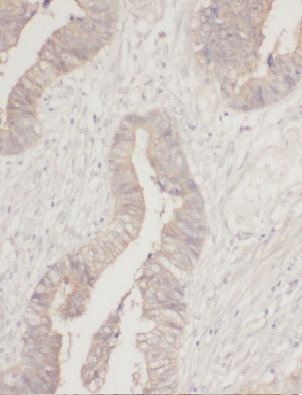

Immunohistochemistry of paraffin-embedded human colon cancer using FNab05402(MTHFD1L antibody) at dilution of 1:100 IP Result of anti-MTHFD1L (IP:FNab05402, 4ug; Detection:FNab05402 1:1000) with HeLa cells lysate 2000ug.